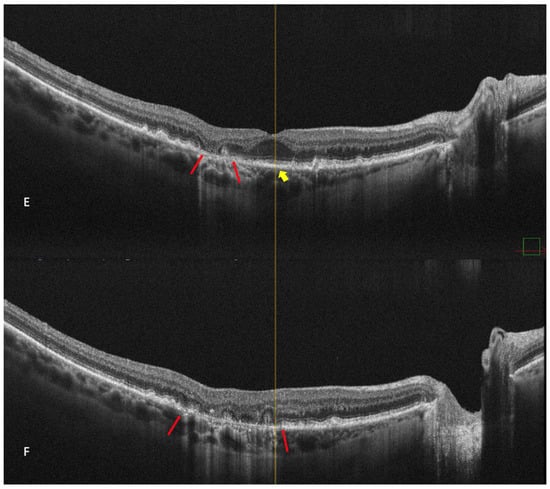

Retromode illumination imaging modality’s ability to detect changes in the retina that appear in wet AMD was evaluated by Pilotto et al. [45]. Neuroretinal detachment (NRD) can be seen on the retromode image as an elevated area (62.5% sensibility; 66.7% specificity) [45]. Pigment epithelium detachment (PED) can be detected with retromode illumination as an elevated area (100% sensibility; 69% specificity) [45]. Cystoid macular edema (CME—See Figure 7) is another entity well-detected with retromode illumination (87.5% sensibility; 100% specificity) [45]. Epiretinal membrane was well-detected with retromode (66.7% sensibility; 100% specificity) [45].

CME was described on the retromode images as polygonal or oval cystoid spaces [48] or as a “honeycomb”-like pattern with a central, large, cell-like element (Figure 7) [45].